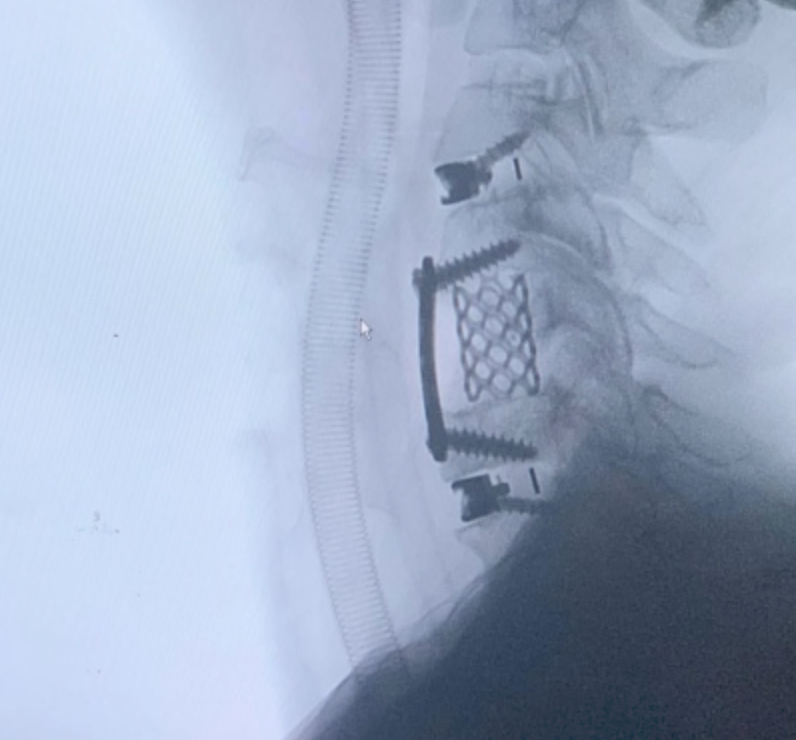

Cada procedimiento requiere una planificación detallada, basada en estudios de imagen y evaluación clínica, con el objetivo de lograr una descompresión adecuada de estructuras nerviosas y restaurar la estabilidad vertebral.

Se emplean técnicas quirúrgicas modernas, incluyendo abordajes mínimamente invasivos cuando son viables, lo que permite una recuperación más rápida y menor impacto en el paciente.